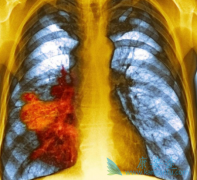

在中国这个吸烟大国, 肺癌 可是被称为“癌症第一杀手”。在过去的三十年间,我国肺癌患者死亡率上升了465%,肺癌也因此成为上升速度最快的癌症,并且已取代肝癌成为我国癌症导致死亡的首要原因。   肺癌主要分为非小细胞肺癌和小细胞肺癌两种,其中非 ...